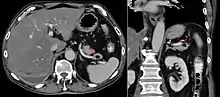

Macrocephaly is a condition in which circumference of the human head is abnormally large.[1] It may be pathological or harmless, and can be a familial genetic characteristic. People diagnosed with macrocephaly will receive further medical tests to determine whether the syndrome is accompanied by particular disorders. Those with benign or familial macrocephaly are considered to have megalencephaly.

Many people with abnormally large heads or large skulls are healthy, but macrocephaly may be pathological. Pathologic macrocephaly may be due to megalencephaly (enlarged brain), hydrocephalus (abnormally increased cerebrospinal fluid), cranial hyperostosis (bone overgrowth), and other conditions. Pathologic macrocephaly is called "syndromic", when it is associated with any other noteworthy condition, and "nonsyndromic" otherwise. Pathologic macrocephaly may be caused by congenital anatomic abnormalities, genetic conditions, or by environmental events.[3]

Macrocephaly is customarily diagnosed if head circumference is greater than two standard deviations (SDs) above the mean.[11] Relative macrocephaly occurs if the measure is less than two SDs above the mean, but is disproportionately above that when ethnicity and stature are considered. Diagnosis can be determined in utero or can be determined within 18–24 months after birth in some cases where head circumference tends to stabilize in infants.[12] Diagnosis in infants includes measuring the circumference of the child's head and comparing how significant it falls above the 97.5 percentile of children similar to their demographic. If falling above the 97.5th percentile then the patient will be checked to determine whether there is any intracranial pressure present and whether or not immediate surgery is needed.[2] If immediate surgery is not needed then further testing will be done to determine whether the patient has either macrocephaly or benign macrocephaly.